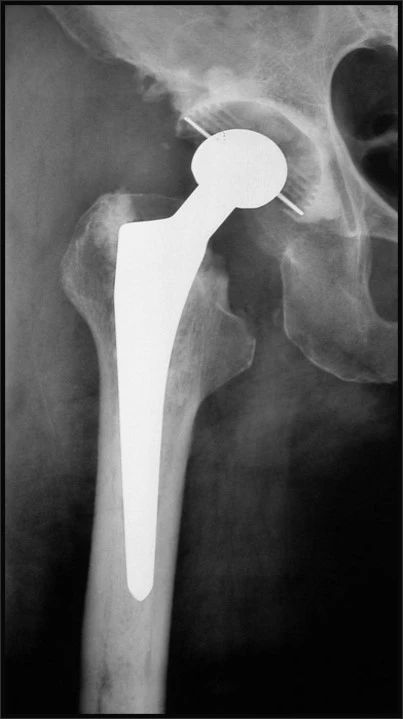

股骨柄的种类

Khanuja按几何形学分类:

- 1.单楔形

- 2.双楔形

- 3A,锥形圆柄

- 3B,锥形纵槽柄

- 3C,锥-矩形柄

- 4,全涂层柱形柄

- 5,组合式假体

- 6,曲形解剖设计

按固定方式分类:

近端稳定

远端稳定

全段稳定

初期稳定:近端或远端的压配

长期一定是依靠柄的涂层